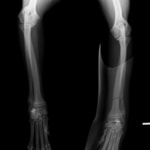

症例3:キルシュナーワイヤーのピンニングによる整復

ペルシャ猫 11ヶ月齢 雄

他院にて左大腿骨遠位の成長板骨折(salter-harrisⅠ型)が認められており、治療相談を目的として来院。当院にて、キルシュナーワイヤーを用いたピンニングにより骨折部位の整復を行いました。術後の経過は良好で、現在も経過観察中です。

術前レントゲン

術後レントゲン